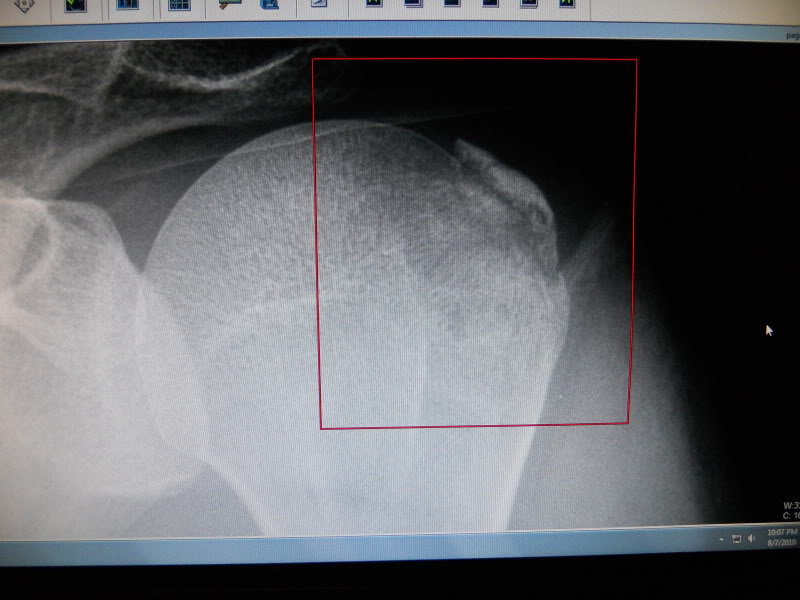

The 12:1 comp piston is a beast to kick over...my foot slipped offed, and it fired sending the kickstarter at Warp Factor 10 into the back of my calf

I'm still limping around from that!![]()